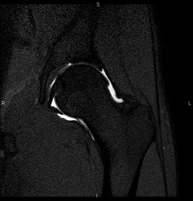

Exploración para el estudio de lesiones en tendones, músculos y articulaciones coxofemorales. Permite identificar de forma precoz la artrosis de cadera. Resulta muy útil para detectar las bursitis y la osteopatía dinámica del pubis, frecuente en deportistas. Tiene una duración aproximada de 20 minutos. No emplea radiación ionizante. - RM Sacroilíacas

Exploración para el estudio de las lesiones en pequeñas estructuras anatómicas de sus articulaciones tales como ligamentos y cartílago. El estudio viene precedido por una inyección de contraste en el interior de una de las articulaciones, realizada bajo control de rayos X. La duración global de los dos procedimientos es de 50 minutos. - Artro-RM Cadera

Exploración para el estudio de las lesiones en pequeñas estructuras anatómicas de la articulación que suelen lesionarse en pacientes que sufren luxación o pinzamiento (disminución del espacio). El estudio viene precedido por una inyección de contraste en el interior de la articulación, realizada bajo control de rayos X. La duración global de los dos procedimientos es de 50 minutos. - Artro-RM Rodilla